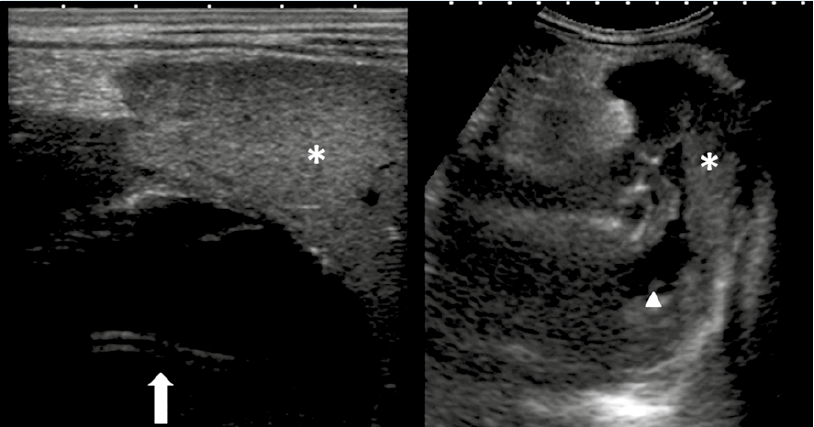

Con el diagnóstico de neumonía basal izquierda se decidió hospitalizarlo para tratamiento antibiótico intravenoso con ampicilina (150 mg/kg/ día) y administración de oxígeno. Al tercer día, por persistencia de los síntomas, se solicitó una ecografía abdominal en la que se observó una lesión quística intraesplénica de gran tamaño (aproximadamente 113 x 103 x 116 mm), hipoecogénica y homogénea (Figura 1). Se realizó una punción-aspiración guiada y se dejó un catéter tipo pigtail en el interior (Figura 2), con mejoría clínica y analítica inmediata.

En el cultivo del absceso creció Salmonella serogrupo D. El drenaje permaneció durante 10 días; los datos clínicos reaparecieron a los 5 días del retiro del catéter, con un nuevo pico febril y aumento de las necesidades de oxígeno

suplementario. Ante la confirmación ecográfica del aumento del tamaño de la colección líquida intraesplénica y hepatización del lóbulo inferior izquierdo pulmonar, se decidió una tomografía computada (Figura 3) para definir la localización exacta de la lesión y su relación con las estructuras vecinas. Se volvió a drenar guiándose con control ecográfico y se programó para capsulectomía definitiva. En la intervención se encontraron una lesión grande encapsulada en la región anterior del bazo, en relación directa con el ligamento gastrocólico y la cúpula vesical, de contenido mixto purulento-sanguinolento. Se efectuaron la extirpación quística parcial y la fenestración de la cápsula. El análisis anato mopatológico de la pieza fue compatible con quiste epitelial primario.

La aspiración percutánea guiada por ecografía, con colocación de catéter, junto con la cobertura antibiótica apropiada, es una técnica fiable con una alta tasa de éxito, sobre todo si el contenido es suficientemente líquido, sin septos ni restos necróticos.18 Este procedimiento es muy practicado como medida temporal en pacientes inestables o críticamente enfermos porque por lo general consigue que la recuperación sea rápida en la condición del paciente.19 El problema que plantea es la alta tasa de recurrencia, por persistencia del revestimiento epitelial, que disminuye al asociarse la escleroterapia.20Además, puede producir adherencias con los órganos adyacentes y una densa respuesta inflamatoria alrededor del bazo. Con nuestro caso demostramos que, si el drenaje percutáneo es insuficiente para una curación total, se mantiene como primera etapa de intervención válida, aumentando las posibilidades de éxito de la cirugía, al disminuir el tamaño de la lesión y eliminar el contenido purulento.